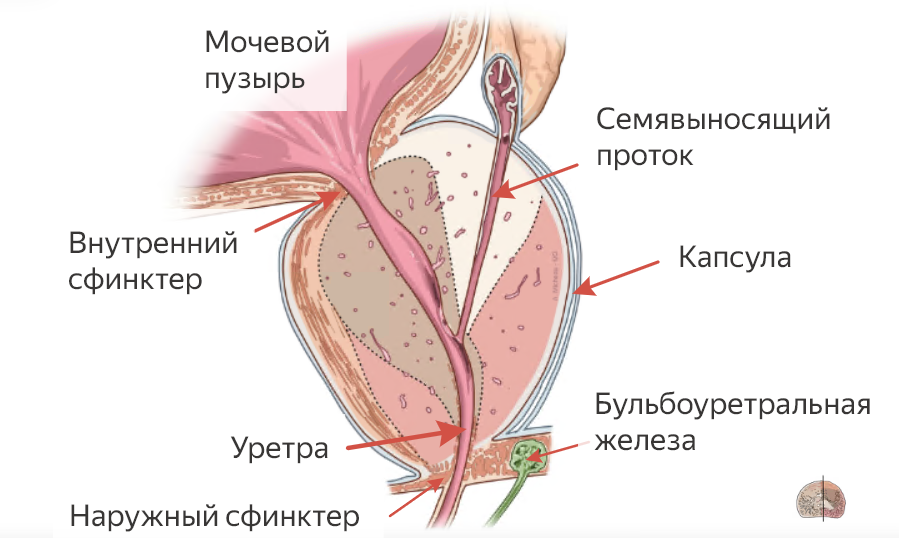

Простата (предстательная железа) расположена под мочевым пузырем внутри капсулы простаты и охватывает уретру (мочеиспускательный канал) со всех сторон. Поэтому разрастание ткани простаты приводит к сужению уретры за счет ее механического сдавливания окружающей тканью. Простата растет всю жизнь, точно так, как всю жизнь растут волосы и ногти. Особенно быстрый рост начинается с возраста 40-50 лет. Увеличение простаты может быть физиологическим (связанным с возрастом) или патологическим, когда возникает доброкачественная гиперплазия предстательной железы — ДГПЖ.

В случае же ДГПЖ удаляется только аденома, т.е. разросшаяся ткань внутри капсулы простаты, с максимальным сохранением органов, влияющих на половые функции. В частности, сохраняются семенные пузырьки, которые вырабатывают 70% спермы, нервы, отвечающие за эрекцию (они расположены снаружи капсулы), семенной бугорок, семявыносящие протоки.

ретроградная эякуляция (не в уретру, а в мочевой пузырь). Причина в том, что по методике ТУР удаляется сфинктер, который в норме закрывает доступ спермы в мочевой пузырь;

недержание мочи – у 1-2% пациентов по причине удаления внутреннего сфинктера во время операции и недостаточной функции внешнего сфинктера;